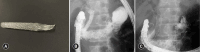

Approximately 60% of pancreatic cancers occur in the pancreatic head and may present as obstructive jaundice due to bile duct invasion. Obstructive jaundice often leads to poor general conditions and acute cholangitis, interfering with surgery and chemotherapy and requiring biliary drainage. The first choice of treatment for biliary drainage is the endoscopic transpapillary approach. In unresectable tumors, self-expandable metal stents (SEMSs) are most commonly used and are classified into uncovered and covered SEMSs. Recently, antireflux metal stents and large- or small-diameter SEMSs have become commercially available, and their usefulness has been reported. Plastic stents are infrequently used in patients with resectable biliary obstruction; however, owing to the recent trend in preoperative chemotherapy, SEMSs are frequently used because of the long time to recurrent biliary obstruction. Endoscopic ultrasound-guided biliary drainage (EUS-BD) is often performed in patients who are not eligible for the transpapillary approach, and favorable outcomes have been reported. Different EUS-BD techniques and specialized stents have been developed and can be safely used in high-volume centers. The indications for EUS-BD are expected to further expand in the future.